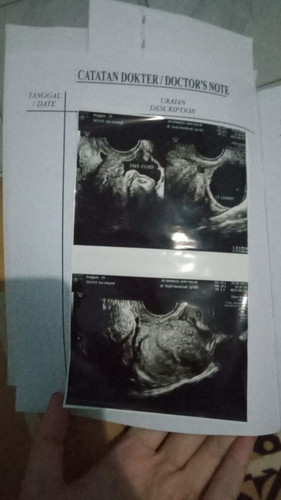

Saya hamil 4 minggu 4 hari. Tdi usg karna mau sekalian konsul, karna pernah keguguran di minggu ke 6. Hasil usg kantong janin belum terlhat. Malah ada hitam2 yg kemungkinan akan pendarahan, atau bisa jadi normal. Karna pagi nya saya ngeflek sedikit, jdi dikasih vitamin dan disuruh bedrest 1 minggu sampai mau usg kembali. Bunda bunda pernah mengalami ga? Dan bagaimana hasilnya? #bantusharing #ingintahu #pleasehelp #firstmom #firstbaby